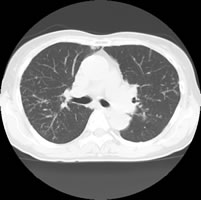

CT画像

• ct01

• ct02

• ct03

• ct04

喫煙者向けの測定

Risk Pointer

胸部CTを撮影したデーターよりCOPD(慢性閉塞性肺疾患)の評価ができます。

LAA解析(Low Attenuation Areaの略で、低吸収領域を示す)により

LAA分布(CT画像上の黄色い部分=肺胞にダメージのある部分) がわかりやすく禁煙指導に有用です。